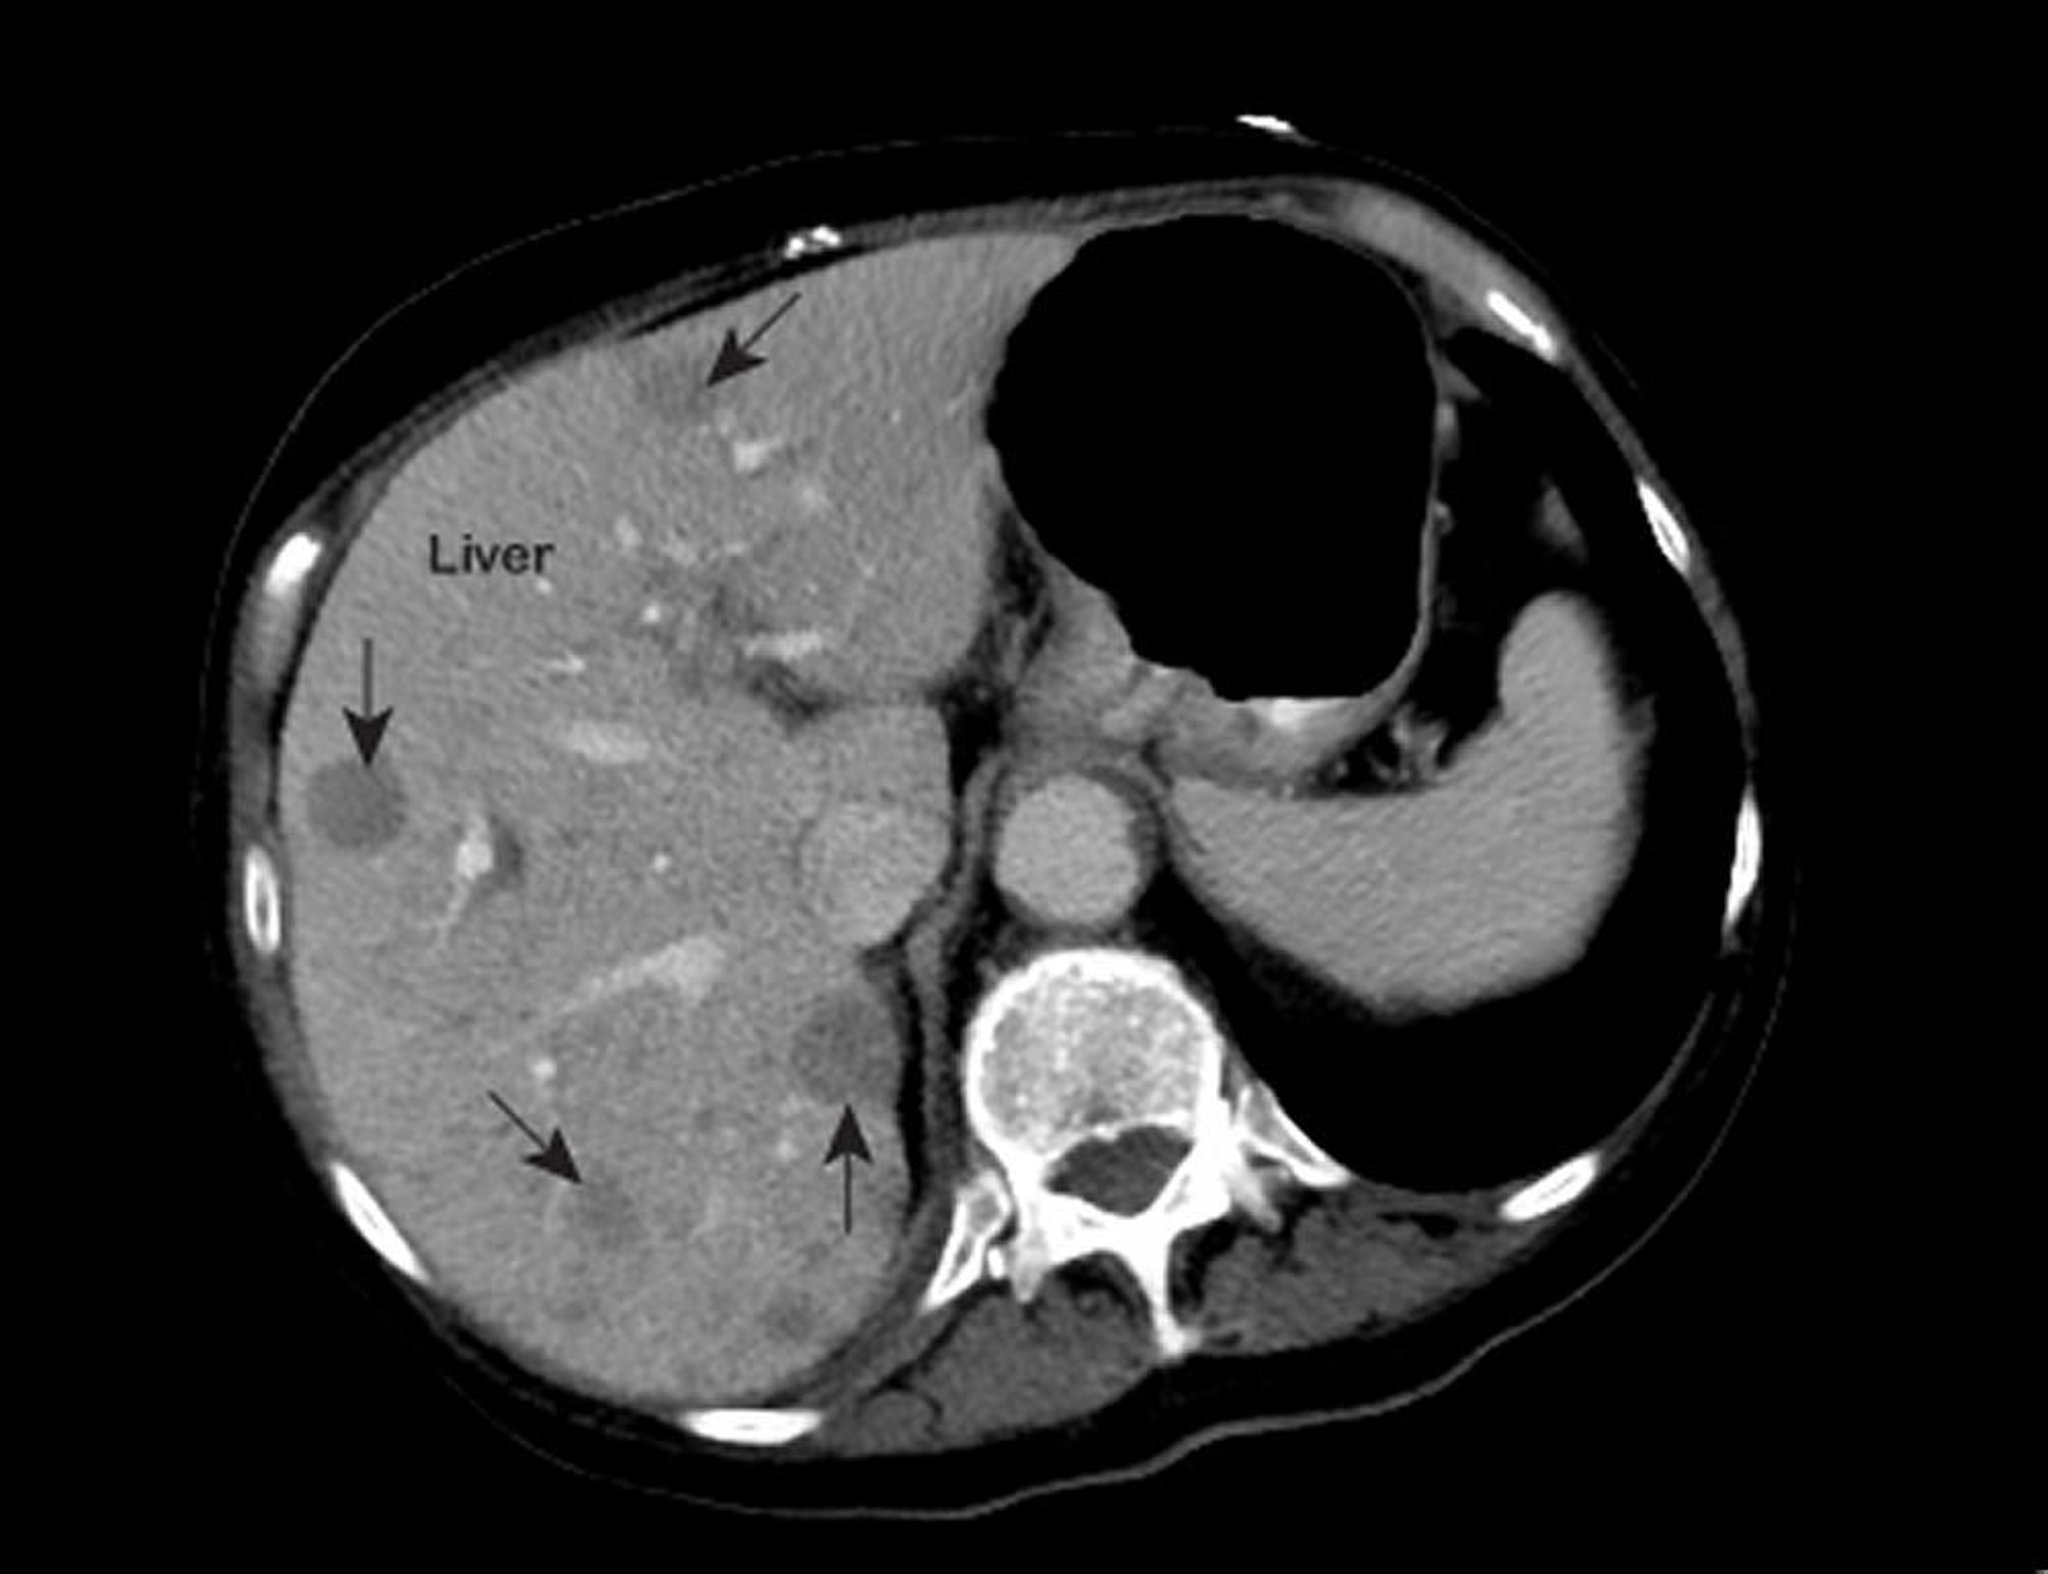

Lebermetastasen

Eine auffällige MRT-Aufnahme der Brust zeigt abweichende Stellen (mit Pfeilen gekennzeichnet) in der Leber. Diese Befunde sind typisch für Lebermetastasen.

Bild mit freundlicher Genehmigung von Dr. med. Patrick O’Kane.